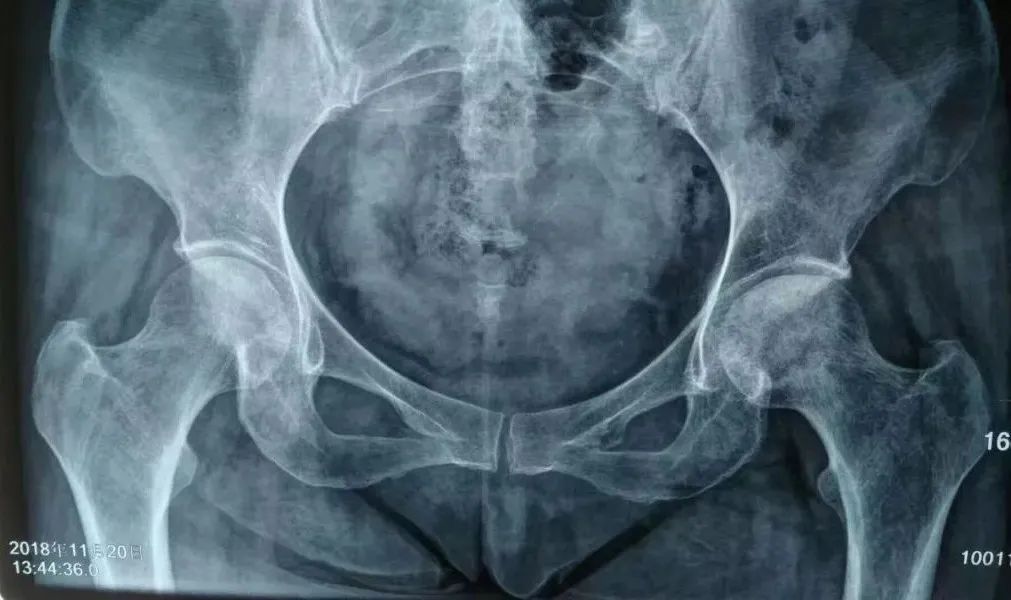

因为股骨头的解剖位置在肌层深处,也是导致早期易误诊的原因。而已经坏死的股骨头对骨细胞的危害即是造成骨细胞的坏死、骨小梁变形、萎缩或已经有虫蚀样改变,点状硬化等,这些都是股骨头坏死的危害所在。